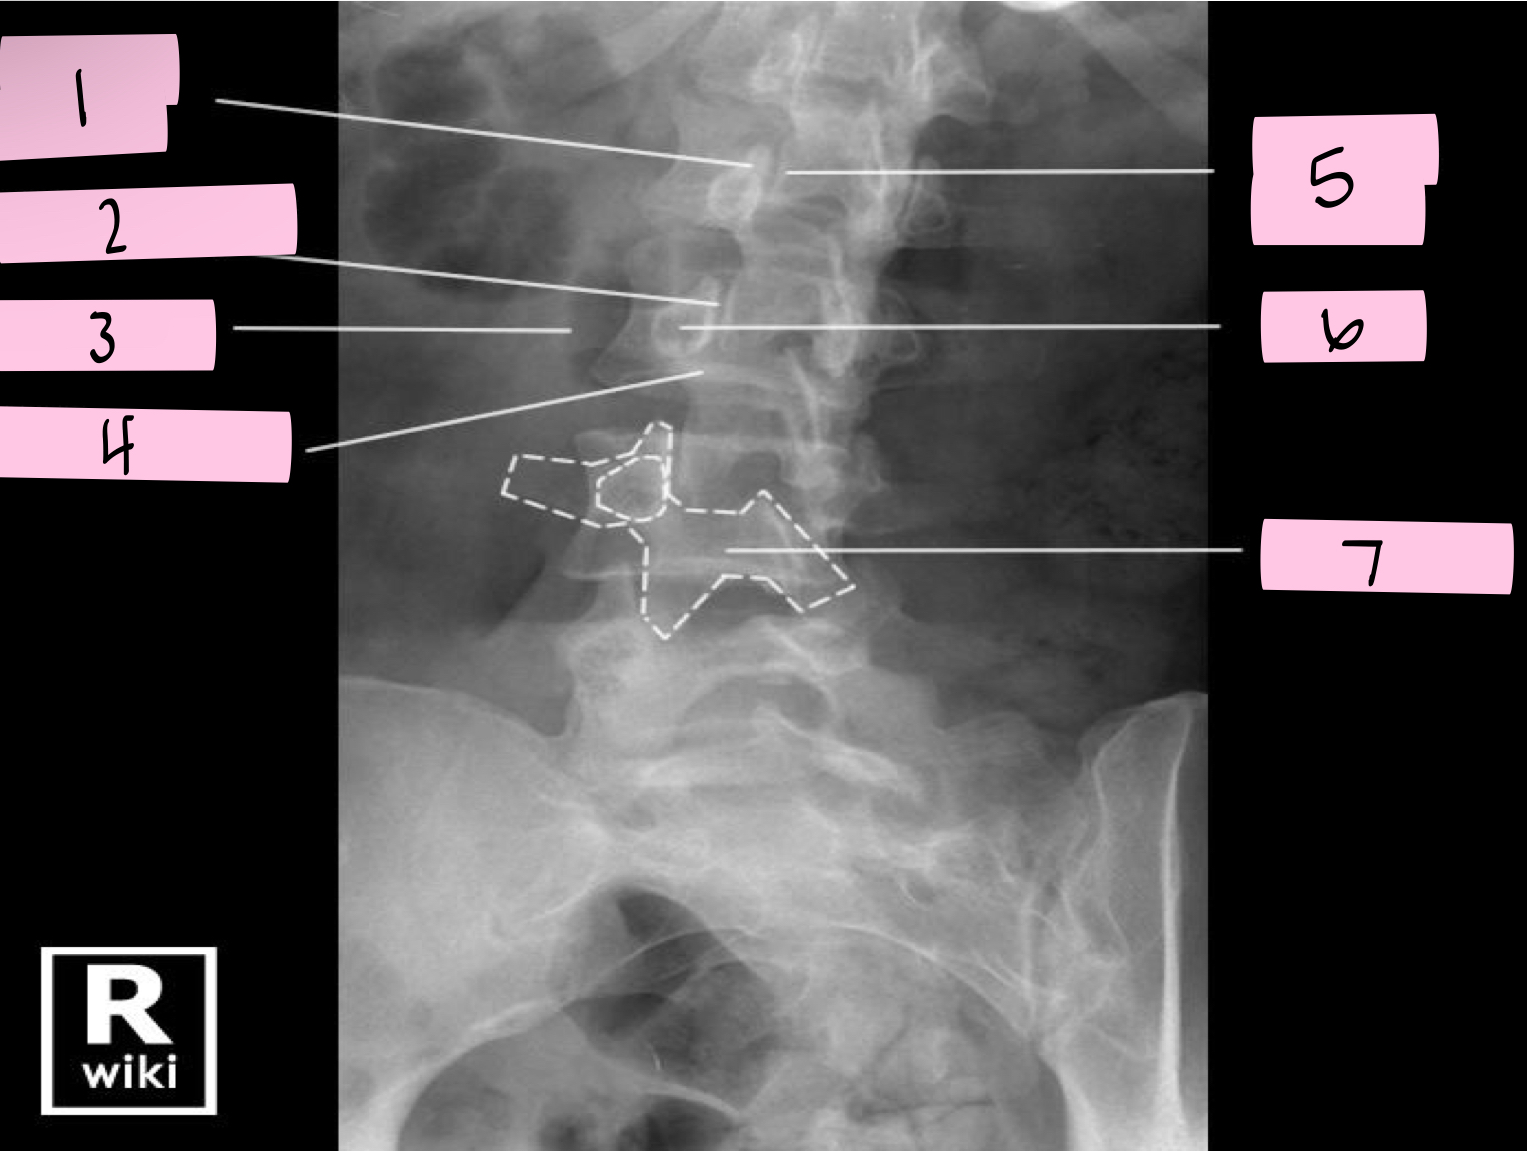

What is 1 pointing to?

Nose- Transverse process

What is 2 pointing to?

Eye- Pedicle

What is 3 pointing to?

Neck- Pars interacticularis (isthmus)

What is 4 pointing to?

Foreleg- Inferior articular process

What is 5 pointing to?

Ear- Superior articular process

What is 6 pointing to?

Tail- Superior articular process of opposite side

What is 7 pointing to?

Body- Lamina and spinous process

What is 8 pointing to?

Hindleg- Inferior articular process of opposite side